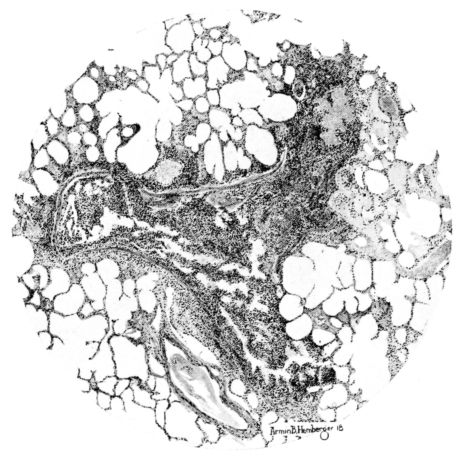

FIG. III. AUTOPSY NO. 90. DRAWING FROM A LESION OF THE TRACHEA (SOMEWHAT OLDER THAN THAT ILLUSTRATED IN FIGURE II). THE MUCOSA IS ENTIRELY LACKING. CONGESTION AND EDEMA ARE THE STRIKING FEATURES IN THE SUBMUCOSA. THE NECROTIZING PROCESS HAS EXTENDED INTO THE MUCUS GLANDS. THIS IS SHOWN IN THE LOWER PICTURE.

The changes are less marked, perhaps, in the trachea than in its finer ramifications. The mucosa is constantly more or less destroyed and large areas, usually focal, are entirely devoid of their epithelial covering. This is replaced by a sparse exudate, composed largely of red blood cells, mucus, a small amount of fibrin, and nuclear fragments (Fig. II). It may dip into the submucosa for a short distance, but usually these indentures are associated with the ducts of the mucous glands into which the inflammatory reaction extends. A more striking feature than the exudate, however, is the edema and the congestion of the submucosa. The loose areolar tissue of the submucosa is spread widely apart, and throughout it distended blood vessels are very conspicuous. Occasionally such a vessel is broken and actual hemorrhage appears in the submucosa. Occasionally, too, the inflammation extends down the duct to the mucous gland itself, and here, also, aplastic inflammatory reaction is evident, inasmuch as the acini now stain intensely red with the cells undifferentiated from each other and specked here and there by broken remains of the dead nuclei (Fig. III). After the disease has continued for a short period, even at the end of five or six days, some regeneration of the epithelial lining may be seen (3) (Fig. IV). But despite this, the acute picture persists, and there goes on, side by side, an attempted repair characterized by epithelial regeneration and the same evidence of acute change. Since the lesion is essentially a superficial one, scars or contractures of any extent are not encountered in the trachea, even in examples of the disease that have ended fatally only after many weeks.[4]